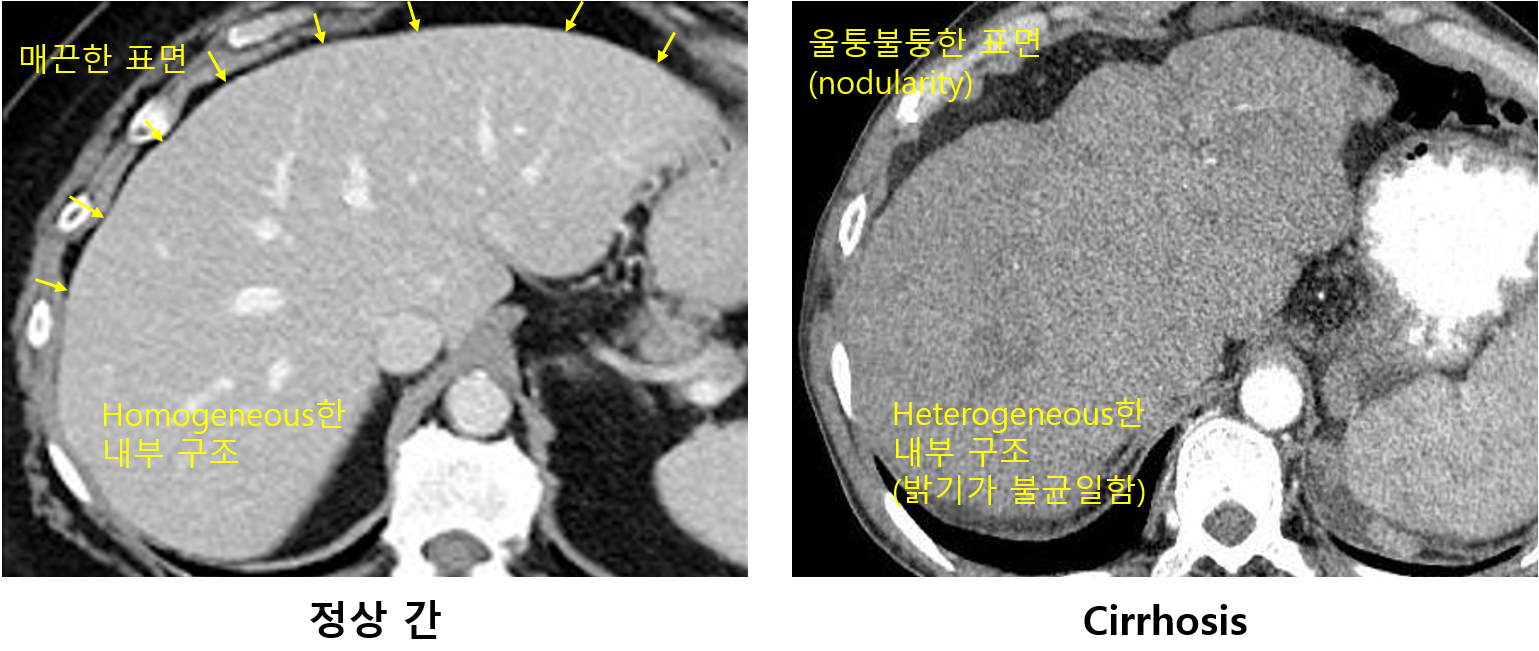

2) 기타 영상검사: US, CT, MRI 등

(1) Nodularity, heterogeneity 등을 확인 가능

(2) LC의 합병증 유무(복수, 식도위정맥류 등), HCC 동반 여부 등을 확인